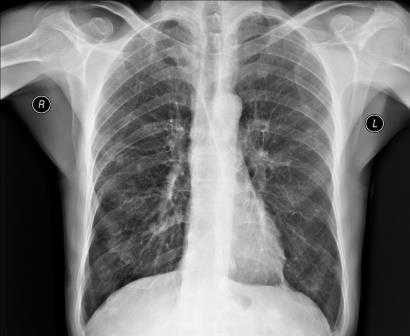

Во время расшифровки полученного рентгеновского снимка, прежде всего, оценивается качество изображения, а значит, и насколько правильно осуществлена процедура. Если рентгенография была сделана в неверной проекции и снимок имеет неточности, то заключение на его основании сделать достаточно сложно. При рентгене легких, например, оценивается размер легких, их форма, структура тканей и легочных полей, состояние воздушности и расположение внутренних органов.

Если у пациента пневмония, на снимке будут видны ярко выраженные отклонения от нормы - интенсивные дополнительные ткани как на прямой, так и на боковой рентгенограмме. Присутствие на снимке особой прикорневой формы, напоминающей по виду крылья бабочки, говорит о венозном застое в области малого круга. На отечность легочной ткани будут указывать неравномерные хлопьевидные затемнения на изображении.

Рентгенография грудной клетки

Рентгенография грудной клетки - это метод диагностики, позволяющий получить изображение органов грудной полости с помощью облучения рентгеновыми лучами. Различные ткани организма в зависимости от своей плотности по-разному пропускают рентгеновы лучи, а значит, по-разному отображаются на снимке (рентгенограмме).

Рентген грудной клетки дает возможность изучить костные структуры (ребра, грудину, позвоночник), легкие, плевру, бронхи и трахею, сердце и средостение, а также оценить состояние мягких тканей этой области.

Прежде всего, рентген грудной клетки используется для диагностики заболеваний легких.

Что показывает рентген грудной клетки?

Рентген грудной клетки способен выявить:

- присутствие в легких очагов воспаления, в том числе характерных для таких заболеваний как пневмония и туберкулёз;

- наличие опухолевых образований и отеков, которые могут быть следствием сердечной недостаточности;

- наличие патологических скоплений газов и жидкостей;

- скопление жидкости в околосердечной сумке, увеличение размера сердца, аорты и лимфатических узлов;

- инородные предметы в легких, пищеводе и дыхательных путях.

Рентген грудной клетки

Рентген грудной клетки назначается в целях диагностики и оценки состояния при таких заболеваниях, как:

- пневмония. В сложных случаях данные рентгена легких являются базовыми для постановки диагноза острой пневмонии;

- туберкулёз;

- воспалительные заболевания плевры (плеврит, эмпиема плевры);

- опухолевые заболевания легких, бронхов, трахеи;

- тромбоэмболия легочной артерии;

- профессиональные заболевания легких, вызванные длительным вдыханием пыли и других мелких частиц;

- пневмотракс (механический разрыв легочной ткани);

- паразитарные заболевания грудной клетки (эхинококкоз);

- заболевания грудного отдела позвоночника.

Рентгенография легких представляет собой снимок грудной клетки в прямой и/или боковых проекциях, позволяющий оценить наличие и степень патологических изменений в легочной ткани.